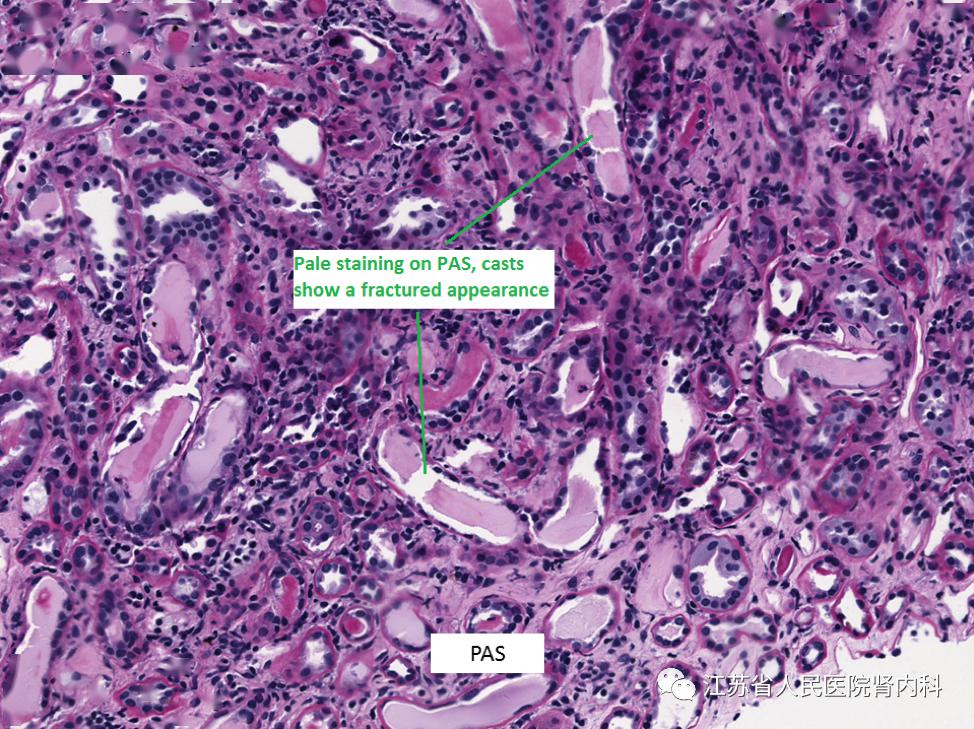

肾脏病理基础(十一)轻链管型肾病

肾脏病理基础十一轻链管型肾病